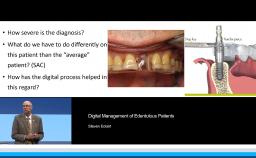

This lecture explains the trends in implant dentistry in a digital world: using digital impressions to obtain milled, printed, or digital casts; designing virtual prostheses via digital diagnostic wax-ups; and incorporating the patient’s cone beam CT into a digital workflow. This practice philosophy embraces prosthodontic-driven treatment planning in completely and partially edentulous arches through identifying the ideal prosthesis and creating prefabricated components. This presentation further demonstrates how this philosophy can lead to uneventful treatment that minimizes complications. The speaker emphasizes the key relationships between teeth, lips, and the residual ridge that indicate the optimal three-dimensional position for implant prostheses, and he advocates for the use of interim prostheses.

- discuss the prosthodontic-driven practice philosophy